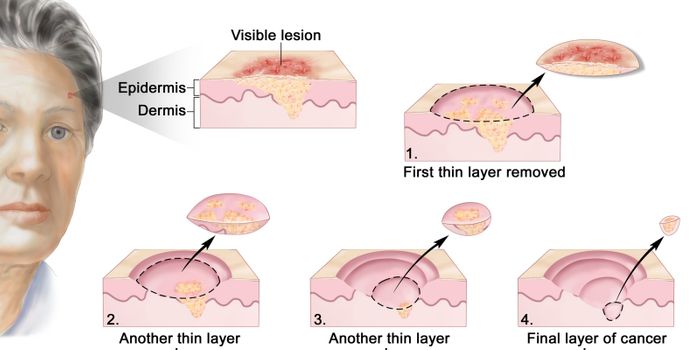

MAY 21, 2019CancerSkin cancer treatment and surgery options vary widely. Even within one method, patients’ needs and surgeons&r ...